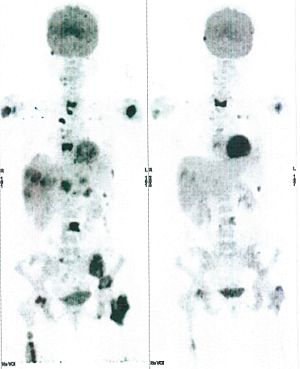

Below are some of the cases, from more than 80 cases we have treated so far with good results. When reading the PET/CT scans, the picture on the left is before treatment, and the picture on the right is after treatment. The intensity of black represents the activity of the cancer, but some black areas are not cancer: brain, heart, radioactive urine in bladder. For the heart, the intensity of black depends on the number of hours of fasting: if more than 10 hours, the heart is not even black, but if fasting is less than 6 hours, it is very black. The intensity of black in the brain can be variable in different scans depending on the brain activity at the time of the scan. The intensity of black in the radioactive urine can also be variable due to the hydration of patients and the time of injection of diuretic.

CASE NO: 1

(HEPATOCELLULAR CARCINOMA + STOMACH CANCER)

A middle-aged women who is very thin and very weak, can hardly walk, lying in bed most of the time. She saw a cancer specialist in a top hospital who discovered that she had massive hepatocellular carcinoma, and another cancer in the stomach. Given that hepatocellular carcinoma is incurable and stomach cancer is very difficult if not impossible to cure without surgery, she was told that nothing could be done for her. She came to ask us to help her. After just 4 treatment, the hepatocellular carcinoma went into remission, and the stomach cancer (arrow) became less active. Until today, more than 6 months later, the hepatocellular carcinoma is still in remission.

CASE NO: 1 - A FEW MONTHS LATER

A few months after successful treatment for hepatocellular carcinoma, and partially successful for stomach cancer, the PET/CT scan showed the stomach cancer becoming very active, with several metastases to the parts of the liver not previously involved by hepatocellular carcinoma. After a few treatment, all the active stomach cancer lesions in the stomach and in the liver went into remission.